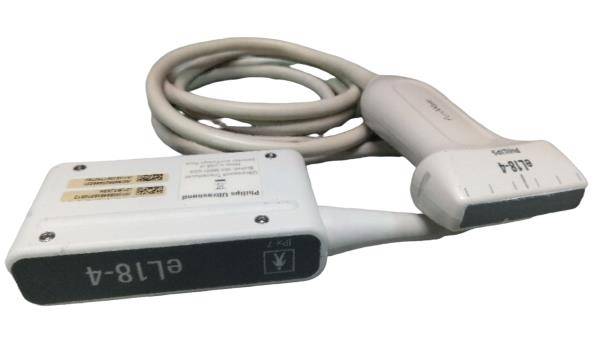

Acuson L5 probe , Ultrasound Transducer Siemens

Sale price$ 1,415.30